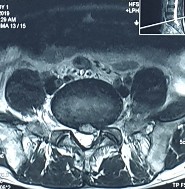

2. Hình ảnh khảo sát dẫn truyền thần kinh, điện cơ đồ và MRI (thực hiện trên mẫu nghiên cứu: bệnh nhân Hoàng Đình H., mã số bệnh nhân 1010320).

Bệnh nhân H., khi khám lâm sàng có biểu hiện tổn thương rễ thần kinh L4, L5, S1. Kết quả xét nghiệm điện cơ thấy: dẫn truyền thần kinh thấy mất phản xạ H, nhưng kết quả khi điện cơ kim có biểu hiện tổn thương rễ thần kinh L5 . Kết quả chụp cộng hưởng từ là tổn thương thoát vị L4 – L5, L5 – S1. Như vậy, trên bệnh nhân này vị trí tổn thương thực tế khi kết hợp phối hợp giữa khám lâm sàng, chẩn đoán hình ảnh và chẩn đoán chức năng là vị trí rễ thần kinh L5.

Hình ảnh thoát vị đĩa đệm trên phim chụp MRI.